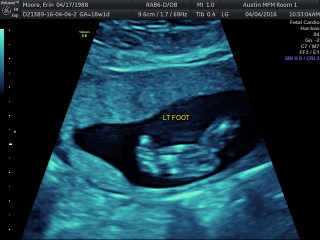

Today we had a super long appointment with Dr. Horton. We had a full anatomy scan of Jackson and ended up not having to do any blood-work, so that was a bonus! While he did not cooperate well for a good 3D face picture, he was in a great position for the echo part of the ultrasound. We got to watch his heart beating for a long time. Even Jordan and I could clearly see all 4 chambers of his heart pumping away. He is about 10″ long, 9 ounces, and has a perfectly beating heart. It was just amazing to watch. We saw 10 fingers and 10 toes, arms and legs, bladder and kidneys, and everything else. We just stared at the screen in excitement and amazement.